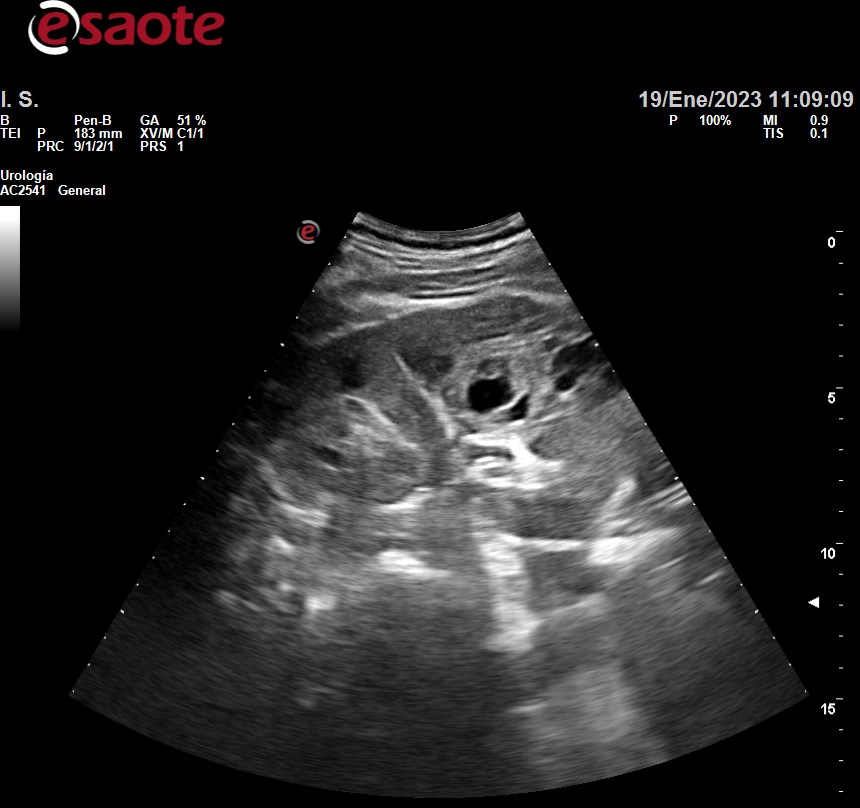

Hallazgos ecográficos

Siguiente hallazgo:

• Riñón derecho aumento tamaño 12.2 x 76.5 x 64.2, irregular, heteroecoico con presencia de áreas hipoecoicas sin litiasis ni dilatación sistema pielocalicial.

Ecografía hospital: tumoración renal derecha primaria, predominantemente sólida con zonas quísticas, en cortical externa interpolar - polar inferior, con proyección al seno renal, sin infiltración del pedículo vascular.